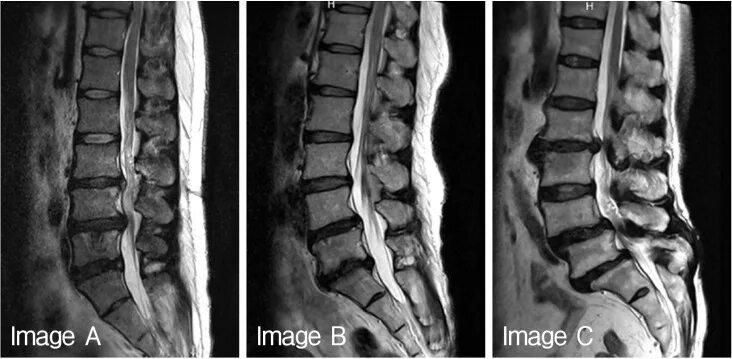

Дегенерация межпозвонкового диска по pfirrmann